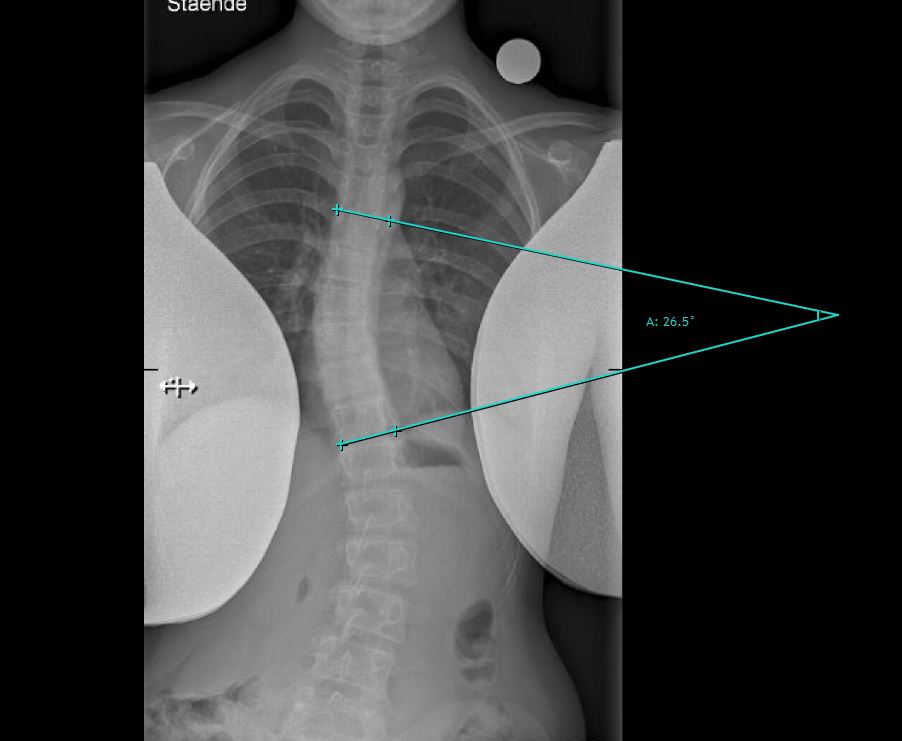

Cobbs vinkel

På dette røntgenbillede ses rygsøjlen bagfra. Der foretages en måling mellem den mest tiltede hvirvel i toppen og bunden af kurven. Der måles fra toppen af den øverste hvirvel og til bunden af den nederste hvirvel.

Ved skæv ryg (skoliose) beregnes ryggens skævhed ved at måle skoliosevinklen også kaldet Cobb's vinkel, som er vinklen mellem linjerne på røntgenbilledet.